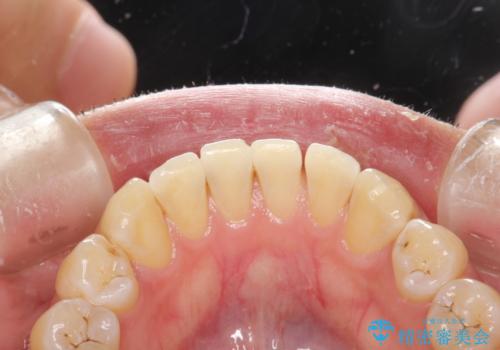

- 歯磨きの際に出血したり、口臭も気になるとのことで来院されました。PMTC30分コースにてクリーニングを行いました。

歯科医院で定期的にクリーニングを行い、歯石除去や細菌に汚染された歯根面の掃除が必要になります。